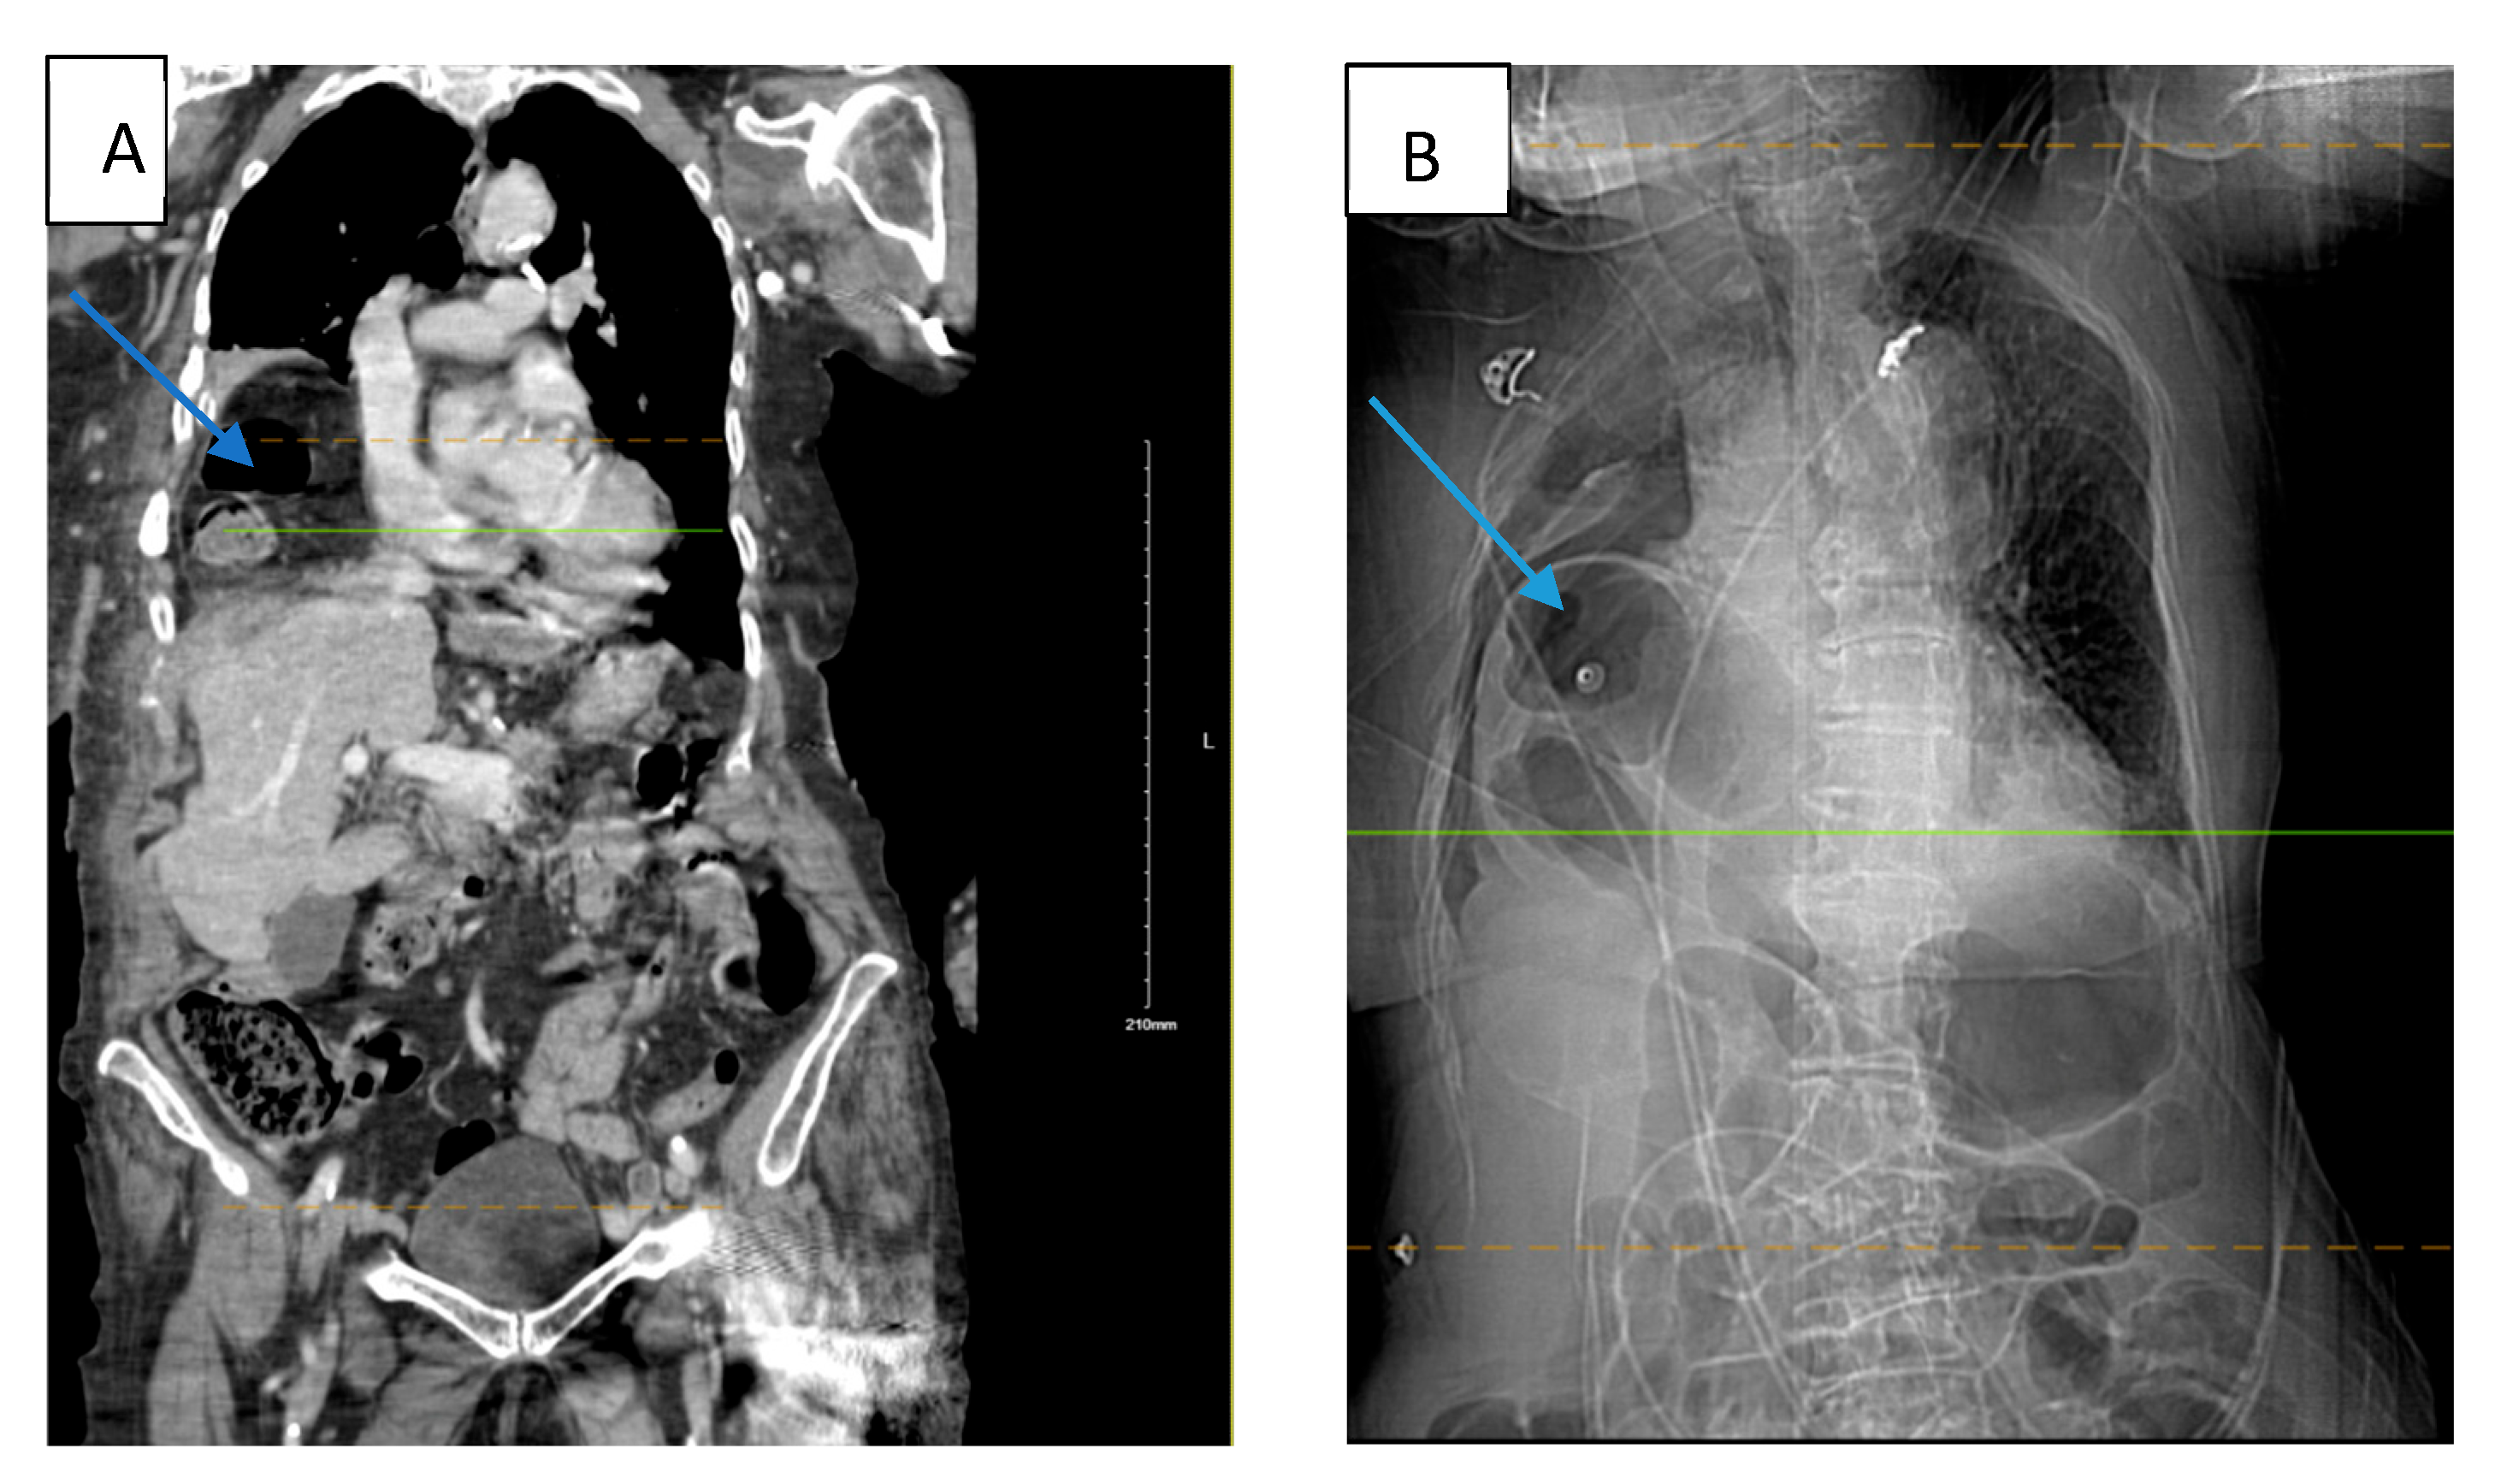

An 88-year-old White American woman with a past medical history of hypertension, hyperlipidemia, and hip fracture with repair (4 years ago) presented to our emergency department (ED) with complaints of pain in her right forearm, left hand, lower back, and on the chest bilaterally with trouble breathing. According to the patient, she had fallen at home 2 days prior. She did not remember how she fell or the precise location but believed she tripped. The patient admitted to an extensive smoking history and likely had undiagnosed chronic obstructive pulmonary disease (COPD). She denied any loss of consciousness, dizziness, or hitting her head. The electrocardiogram (EKG) finding was significant for rapid atrial fibrillation (no prior history) which was managed with an anti-arrhythmic medication throughout her hospital course. The patient was tachycardic, tachypneic, hypotensive with blood pressure (BP) of 96/62 mmHg, and hypoxic to 88% for which she was placed on supplemental oxygen but afebrile in the ED. Physical examination noted tenderness to the right lateral chest with bruising to the right breast and right forearm with an overlying laceration. The abdomen was soft and non-tender. There was no sign of labored breathing. Chest X-ray (CXR) revealed right pleural effusion and areas of atelectasis with several right and lower fractured ribs. Contrast-enhanced computed tomography (CT) of the chest (Figure 1A) showed a perforated right hemidiaphragm with gastrointestinal content in the thorax, mildly displaced acute fractures anterior right third, fourth, and fifth ribs, mildly displaced acute fractures of the right eighth to tenth ribs, and markedly displaced acute fractures of the right sixth to seventh ribs. CT abdomen and pelvis revealed no acute findings. The patient refused surgical intervention. Two days after admission to the surgical intensive care unit (SICU), the patient experienced respiratory distress with the use of accessory muscles to breathe and became hypotensive for which she responded to fluid resuscitation. CT angiogram (CTA) was performed which showed herniation of the bowel into the right anterior chest significantly compromising the right lung volume, pleural effusion, and small pneumothorax (Figure 1B). The patient again refused surgical management and signed a do not intubate and do not resuscitate (DNI/DNR) order. The patient requested comfort care only and died the next day because of her condition. The Injury Severity Score (ISS) recorded for this patient was 29.

Figure 1.

(A) Contrast-enhanced computed tomography (CT) (at the time of admission) of the chest showing a large right diaphragmatic hernia containing hepatic flexure of the colon and omental fat without evidence of strangulation (blue arrow). (B) CTA (two days after admission) revealed a large intestine in the right chest consistent with worsening herniation with the right lung completely collapsed by the herniated colon. Blue arrow in both figures are pointing towards the injury.